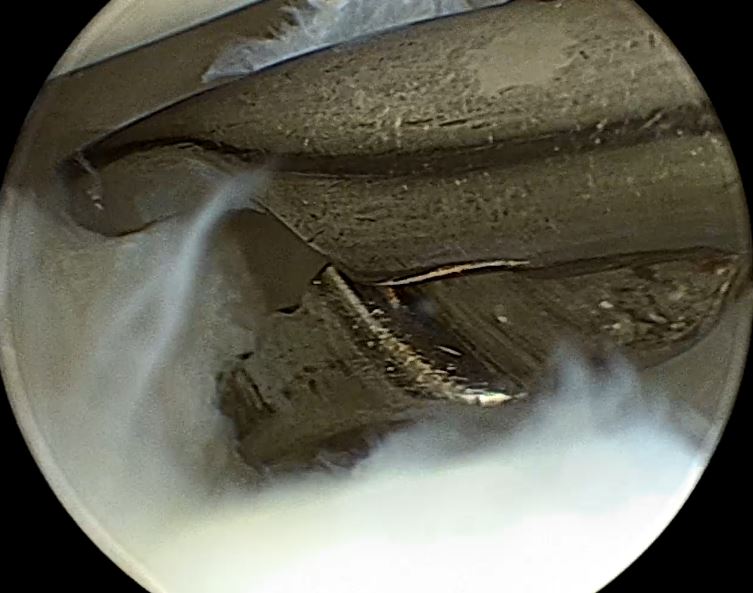

2,女性,32 岁,右膝关节反复弹响,膝关节交锁、疼痛、肿胀。

关节镜下见外侧半月板大厚, 完全覆盖胫骨平台

半月板内部分层撕裂

中央部撕裂